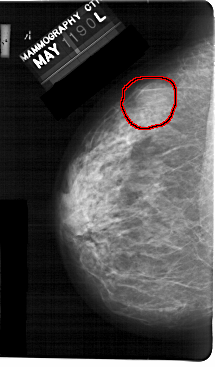

A_1303_1.LEFT_MLO

LEFT_MLO LINES 5491 PIXELS_PER_LINE 3466 BITS_PER_PIXEL 12 RESOLUTION 43.5 OVERLAY

FILE: A_1303_1.LEFT_MLO.OVERLAY

TOTAL_ABNORMALITIES 1

ABNORMALITY 1

LESION_TYPE MASS SHAPE OVAL MARGINS ILL_DEFINED

ASSESSMENT 4

SUBTLETY 4

PATHOLOGY BENIGN

TOTAL_OUTLINES 1

BOUNDARY